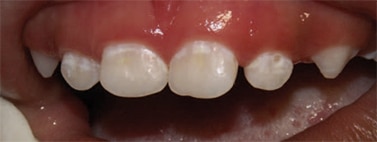

Severe ECC (S-ECC) is defined as any sign of smooth-surface caries in children younger than age 3. Additionally, in children ages 3 through 5, one or more dmf surfaces in primary maxillary anterior teeth, or a dmf score of ≥ 4 (age 3), ≥ 5 (age 4), or ≥ 6 (age 5) surfaces also constitutes S-ECC.3 The typical early sign of ECC is the crescent shaped white spot lesion at the gingival margin (Figure 1 to Figure 4).

Although not approved for caries prevention by the FDA, the American Dental Association (ADA), has recommend fluoride varnish for caries prevention in young patients who are at moderate to high risk.19 The dental community therefore, uses fluoride varnish as “off label efficacy” because of its success in community-based programs. For example, a Kentucky program that used fluoride varnish with 6,000 elementary school students reduced caries incidence from 50% to 11% over 5 years.23 In fact, varnish is used and recommended for children younger than 6.24 Using varnish on white spot lesions— the cardinal first sign of decalcification—has been an important strategy to control ECC.